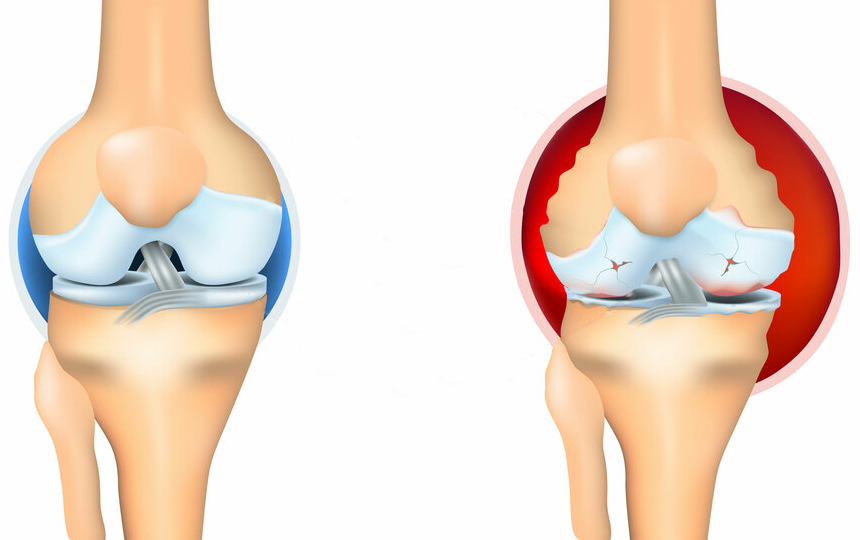

El dolor es una señal importante que indica un proceso patológico en la articulación. Al eliminar solo el dolor, empeoramos la condición de las articulaciones afectadas. El proceso de destrucción se acelera de 3 a 5 veces, lo que finalmente conduce a cambios irreversibles, pérdida total de movilidad y discapacidad.

La causa principal del daño articular es la acumulación de cristales de sal en las articulaciones debido a una circulación sanguínea deficiente y a una mala circulación del líquido sinovial:

- Los cristales de urato son sales del ácido úrico que provocan la gota.

- Los osteofitos son sales calcificadas responsables del 97% de las demás enfermedades articulares y de la columna, como la artritis, artrosis, osteocondrosis, osteoporosis, reumatismo, bursitis e incluso quistes sinoviales.

Estas sales, al depositarse en la superficie de la articulación, actúan como papel de lija, dañando los tejidos circundantes, los huesos y el cartílago. A medida que los cristales crecen, comienzan a dañar los tejidos musculares, los tendones, los vasos sanguíneos y los capilares, provocando inflamación, infección, hinchazón y dolor intenso.

En los casos avanzados, grandes acumulaciones de estas sales pueden romper fácilmente una parte del hueso con un movimiento brusco, lo que lleva a una discapacidad total e inmovilidad permanente de la articulación.